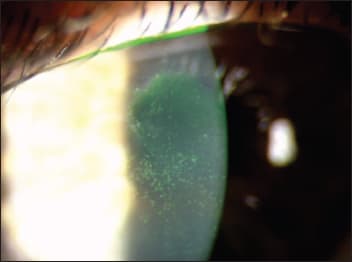

In chronic, more severe stages of dry eye disease, corneal surface damage (such as epithelial damage and staining) results in chronic reductions in visual acuity and contrast sensitivity (Figure 2). In severe cases, reductions can be more easily measured with standard clinical techniques because blinking does not meaningfully improve vision.

Figure 2. Central corneal staining leads to reduced visual performance that is not typically corrected by a blink.